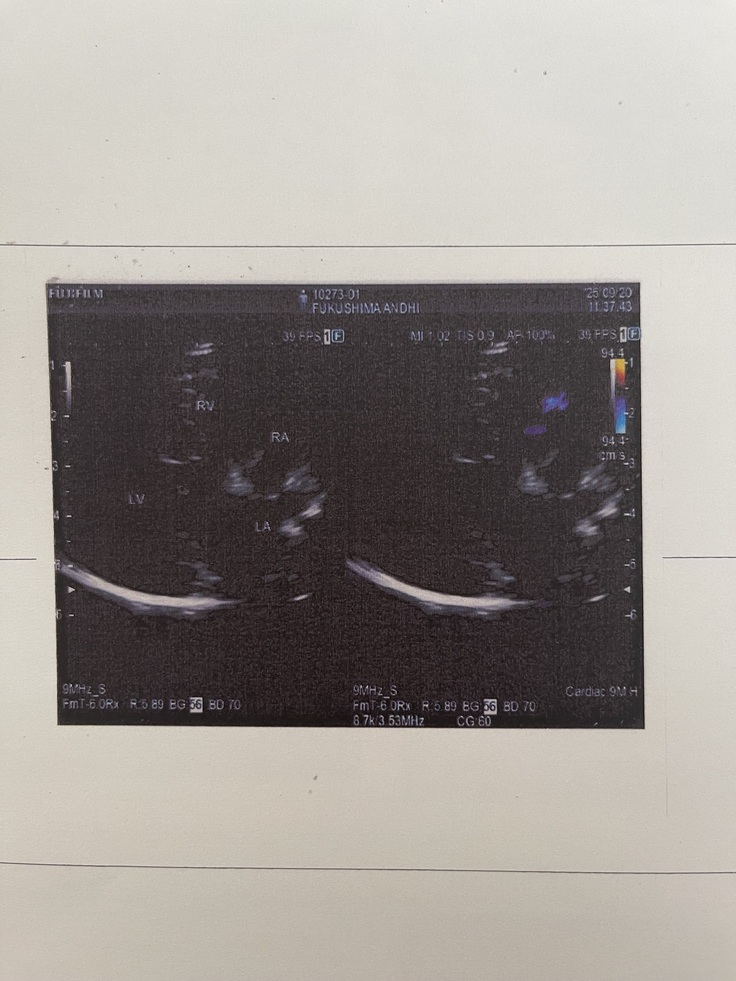

9月20日に、

僧帽弁閉鎖不全症手術の術後6ヶ月検診に

行ってきました🚗🐶

結果、今回も問題なく雑音もほぼない状態で

術後の経過は良好とのことでした☺️✨️✨️✨️✨️

次回は来年3月に術後1年検診です🏥